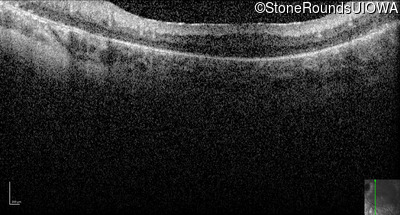

Optical Coherence Tomography - Left -

No Light Perception

Exemplar

Optical Coherence Tomography - Right -